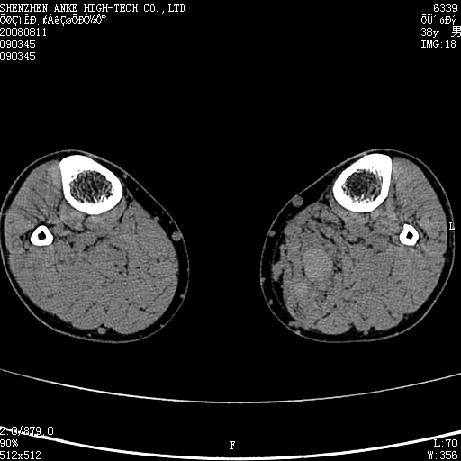

患者,男,38岁,右小腿疼痛性包块1月,查体:右小腿可扪及约5x4cm大小包块,压痛.

左小腿内侧软组织病变,性质待定(血管瘤?);建议行mri检查。